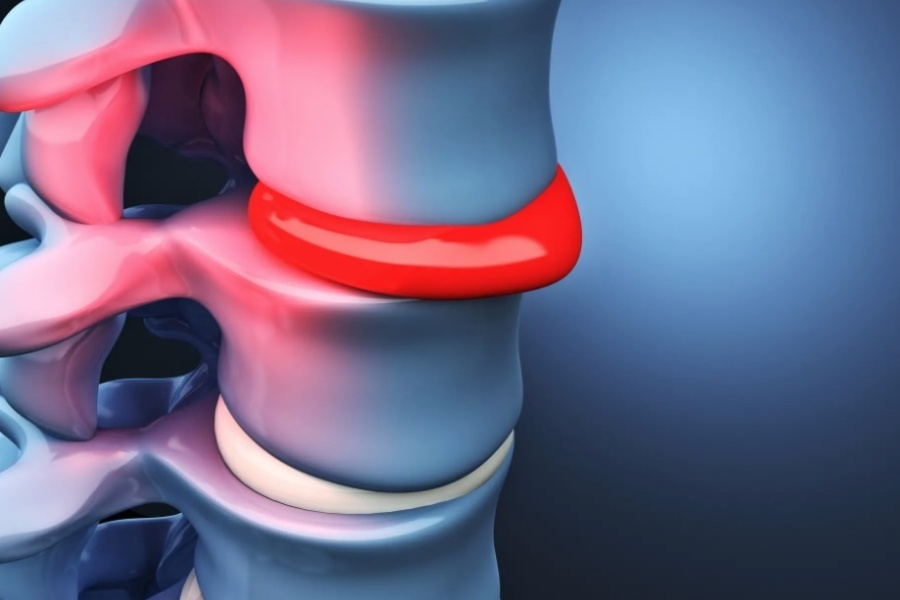

КТ-протрузии дисков: Визуализация и классификация